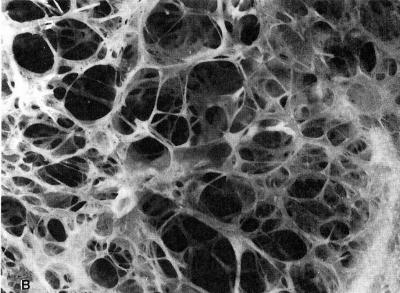

Emphysema, most often brought on by smoking, affects an estimated 60 million people worldwide with more than 3 million sufferers in the United States. There is no cure. It's a chronic, progressive, and irreversible lung disease characterized by the destruction of lung tissue. The loss of the lungs' natural elasticity and the collapse of airways in the lung combine so that the lungs can no longer deflate to let air in. The patient is in a permanent state of "breathlessness" – sucking in rapid, shallow breaths. Even the most nominal physical activities become difficult for emphysema patients and many become dependent on oxygen therapy.

Sterman adds, "Given that emphysema is such a devastating disease associated with permanent destruction of the small air sacs (alveoli) which allow the lungs to function -- any new potential intervention could offer substantial relief to the millions of sufferers in this country."